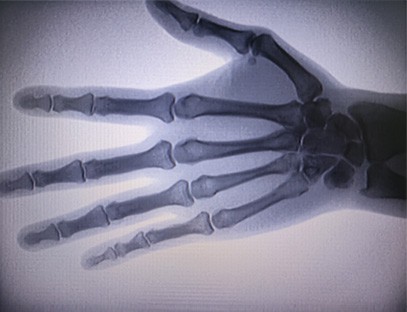

As-c200 kaasaskantav röntgeniaparaat on väikese kiirgusdoosiga ja väga ohutu kaasaskantav instrument. See sobib eriti hästi üksustele ja isikutele, kellel on ebapiisav eelarve ja madalad nõudmised piltidele. Uus põlvkond on varustatud 10-tollise kõrglahutusega suure ekraaniga, millel on suurem perspektiiviulatus ja mis suudab täielikult perspektiivida kogu peopesa. See sobib enamasti meditsiinilise ortopeedilise vaatenurga jaoks. Seda saab ühendada kileprinteriga ortopeediliste kilede printimiseks ning seda saab kasutada ka tööstuslikus tootmises ja katsetamises. Pimeda ruumi puudumine, otsene perspektiiv, vahetu vaatlus, kõrge eraldusvõime ja selge kujutis.

Meie ortopeediline röntgeniaparaat on kvaliteetne toode, mis on loodud spetsiaalselt ortopeediliseks pildistamiseks. Seda saab kasutada erinevate ortopeediliste seisundite, sealhulgas luumurdude, nihestuste, artriidi ja luukasvajate diagnoosimiseks ja ravi planeerimiseks. See on varustatud täiustatud röntgenitehnoloogiaga, mis võimaldab saada kvaliteetseid pilte vähendatud kiirgusega. Masinal on kõrge eraldusvõimega pildisüsteem ja see suudab jäädvustada suure selgusega pilte mis tahes luu struktuurist.